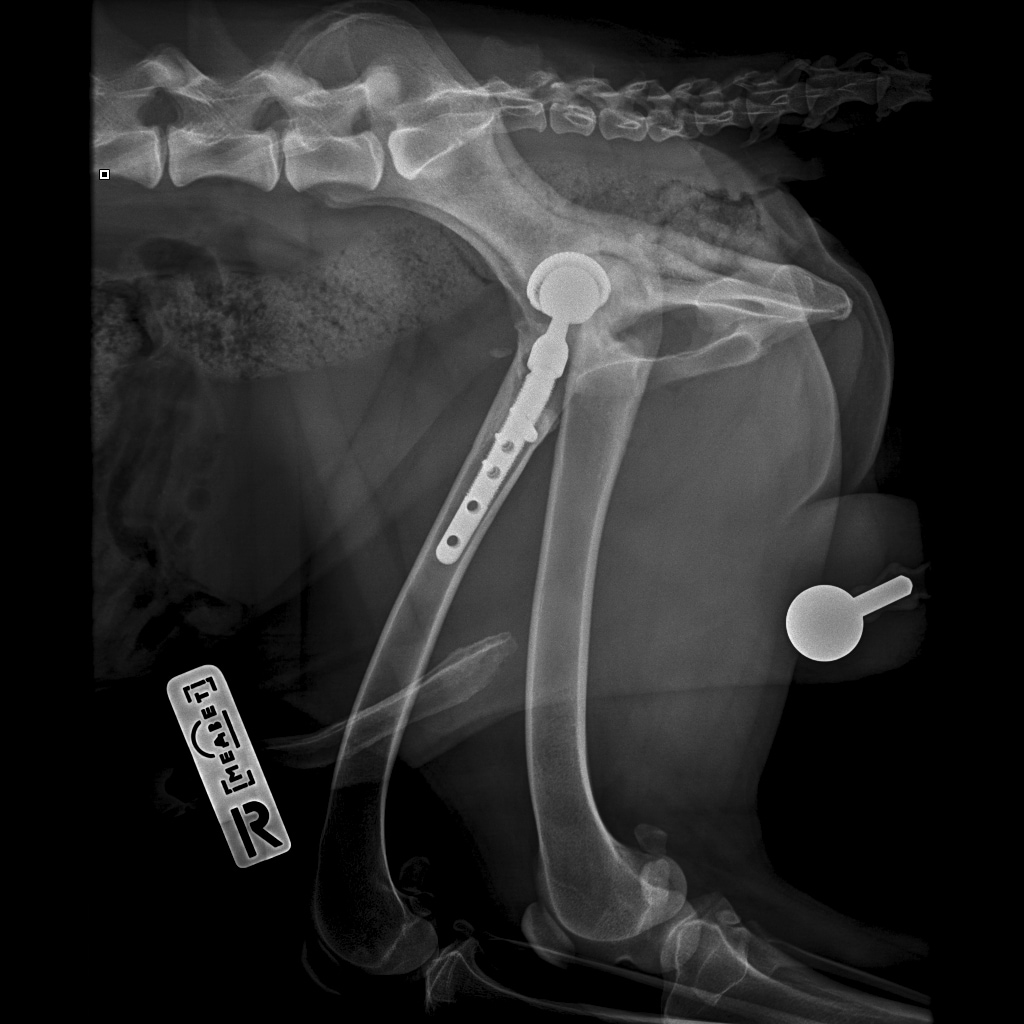

8A836050-66CA-42B2-94D3-F13B288A592B.jpeg

39B2671E-39B9-4502-9E11-ADB169612F24.jpeg

6950B9C9-79EA-4F34-A780-9C3C6BA31B49.jpeg

58C20B18-AA4E-4386-BF83-56CE5E282844.jpeg

Наш металлический мальчик

Железный дровосек